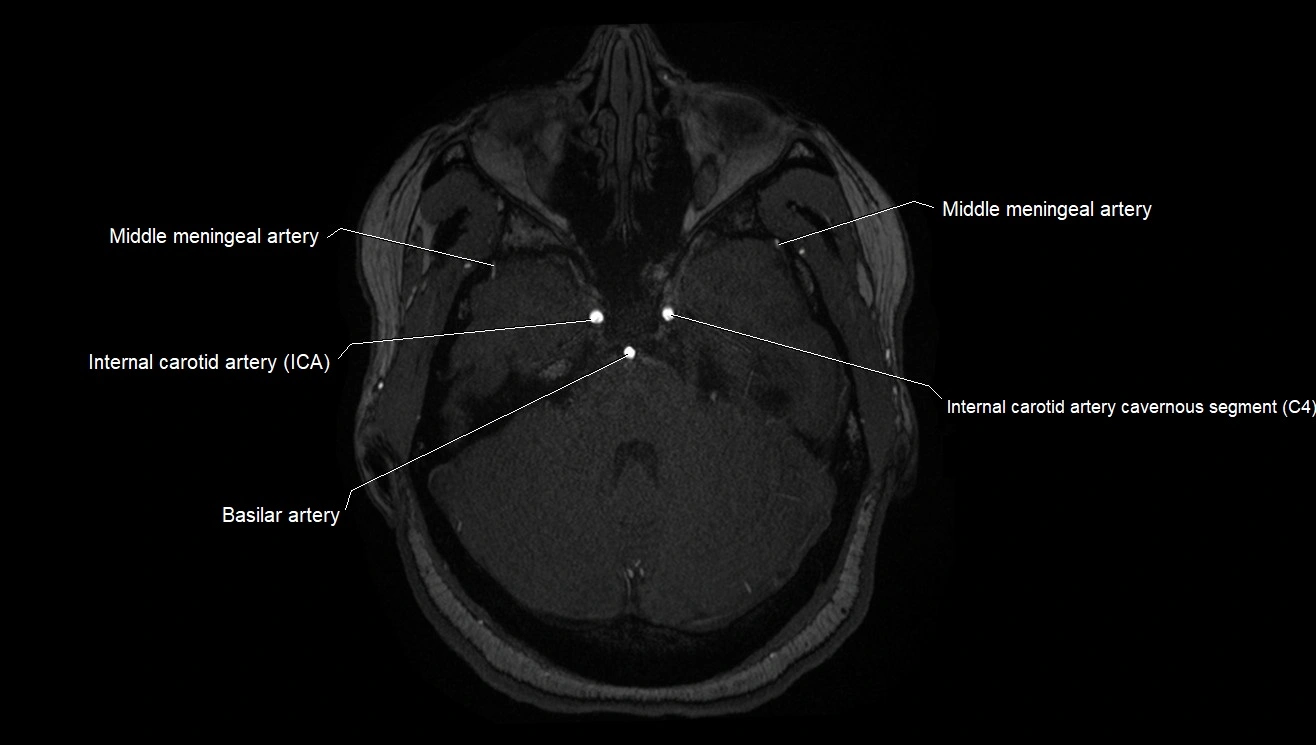

MRA (Magnetic Resonance Angiography):

• Flow-related enhancement makes the AChA appear as a bright, linear vascular signal against suppressed background

• High sensitivity for origin and proximal course; distal branches may be too small to resolve

• Detects stenosis, occlusion, aneurysm, AVM feeders

MRI images

image